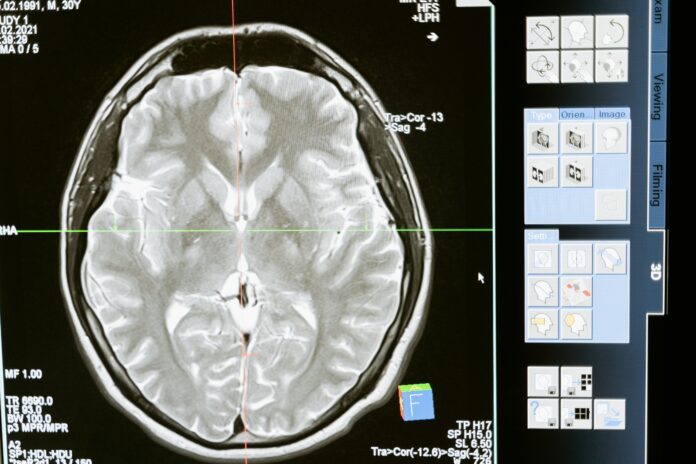

ChatGPT ma problemy z interpretacją wyników laboratoryjnych, wyników obrazowania i pomijał niektóre kluczowe informacje ważne dla diagnozy – napisali autorzy „Oceny ChatGPT jako narzędzia diagnostycznego dla studentów medycyny i klinicystów”